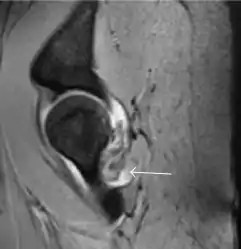

Most of the angles and measurements described in the plain radiograph section can be accurately reproduced on MRI. In addition, the superiority of MRI resolution with intra-articular contrast allows detection of labral and chondral abnormalities that may influence the choice of medical, percutaneous, or surgical management (Figure 9).[1]

Figure 9:

Sagittal T1 weighted image showing anterosuperior labral tear.[1]

Sagittal T1 weighted image showing chondral lesion.[1]

MR arthrography has proven superior in accuracy when compared to native MR imaging. It is considered the best technique to assess the labrum. Knowledge of the normal variable morphology of the labrum helps to differentiate tears from normal variants. A triangular shape is most commonly seen in 66% of asymptomatic volunteers, but round, flattened, and absent labra can also be found in asymptomatic populations. MR arthrography has demonstrated sensitivity over 90% and specificity close to 100% in detecting labral tears. Loose bodies are demonstrated as filling defects surrounded by the hyperintense gadolinium.[1]

Association between labral tears and chondral damage has been demonstrated. This underscores the interaction between cartilage and labrum damage in the progression of osteoarthritis. Chondral damage to the posteroinferior part of the acetabulum as a contrecoup lesion occurs in approximately one-third of pincer cases secondary to persistent abutment on the anterior part of the joint leading to a slight posteroinferior subluxation. This is considered a bad prognosis sign.[1]

MR arthrography can also demonstrate ligamentum teres rupture or capsular laxity, which are debated causes of microinstability of the hip. Elongation of the capsule or injury to the iliofemoral ligament or labrum may be secondary to microtrauma in athletes. MR can demonstrate abnormalities in these cases, such as increased joint volume or a ligamentum teres tear (Figure 9).[1]